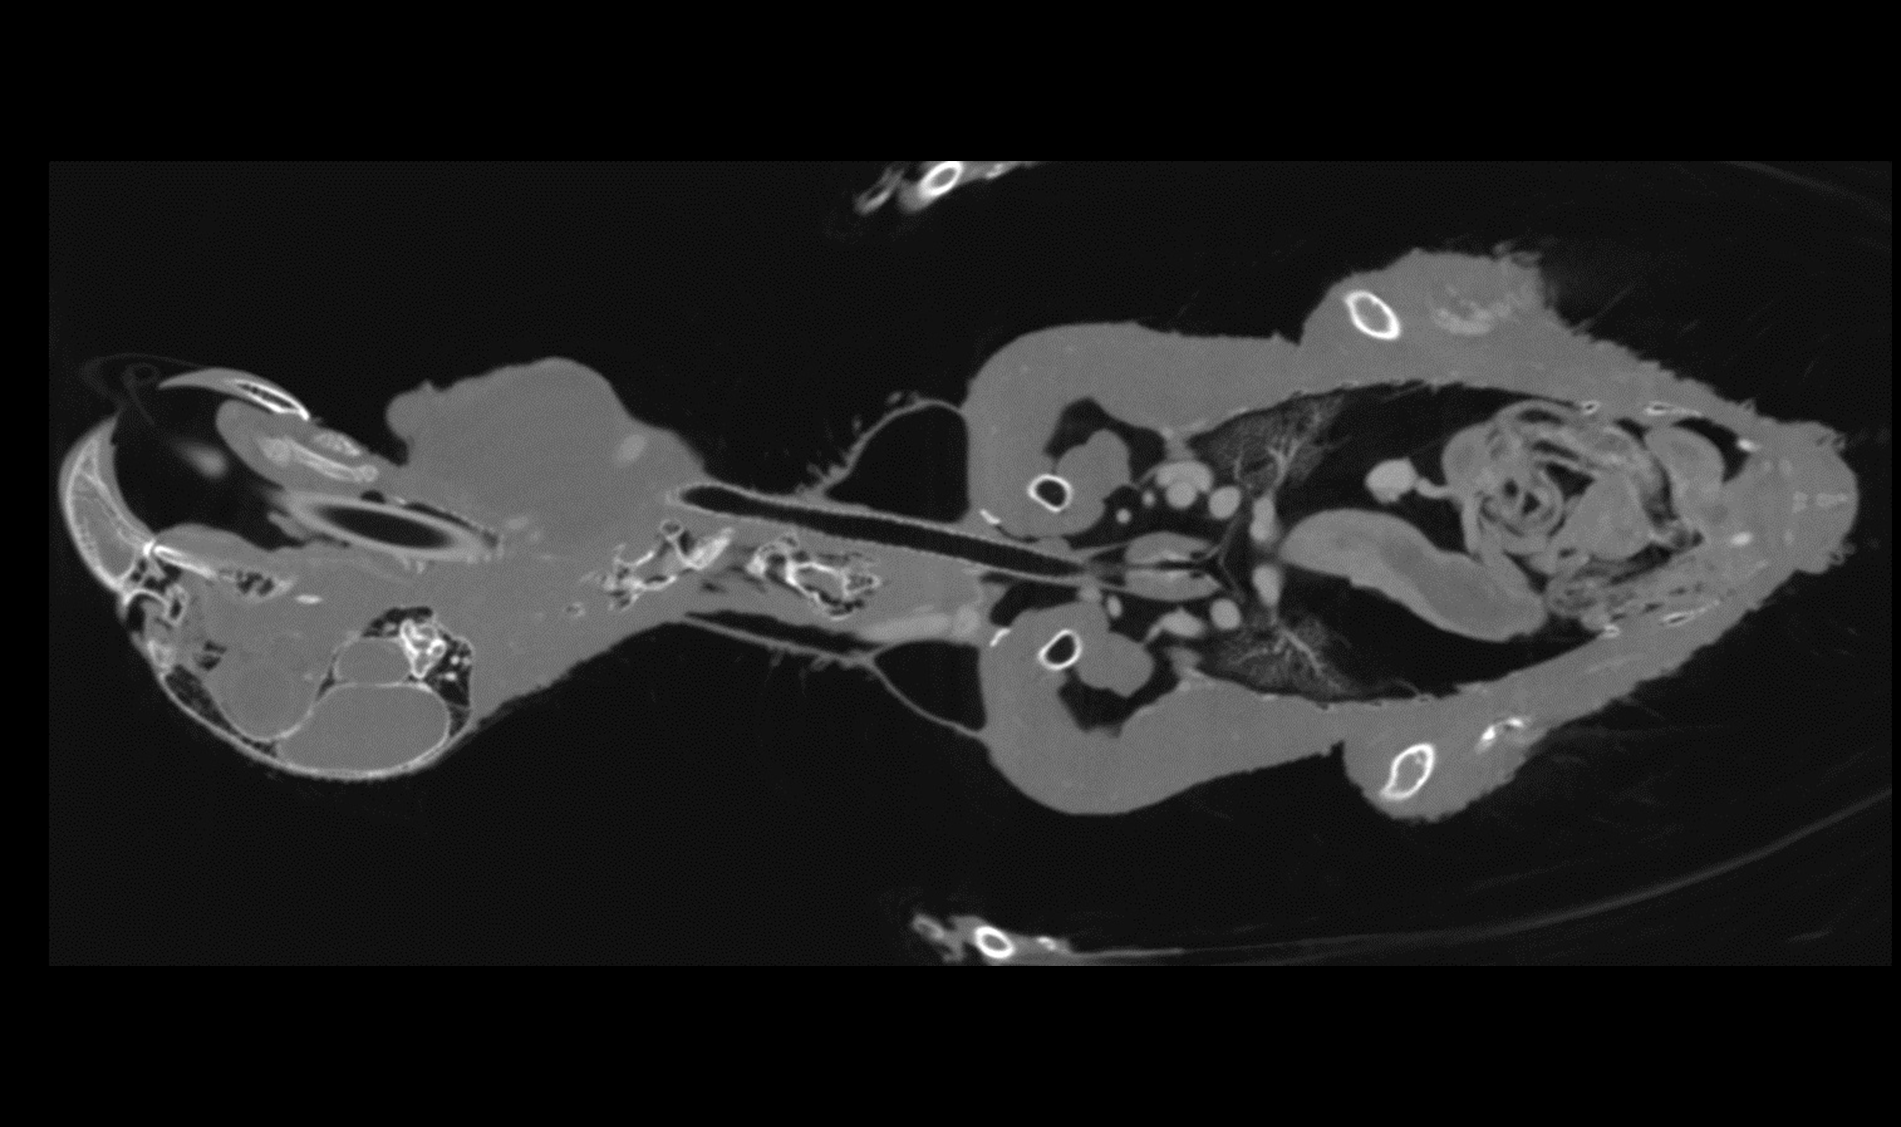

Dr Pedro Armstrong

"Our imaging equipment accommodates animals up to 200 lbs., including the chimpanzee scanned for the Lion Country Safari in Palm Beach County. A case done at the Palm Beach Zoo caught the eye of local news; two recent cases at a private practice will be featured on a national TV show."

DVM, DACVIM,

Mobile Pet Imaging

Dr Scott Echols

"We really don't know that much about the anatomy of a lot of these animals. However, we have never had a way to visualize it like we can now and each scan that we perform is a whole new treasure trove of data. We can literally see each blood vessel in the body."

DVM, DABVP,

Parrish Creek Veterinary Hospital & Diagnostic Center